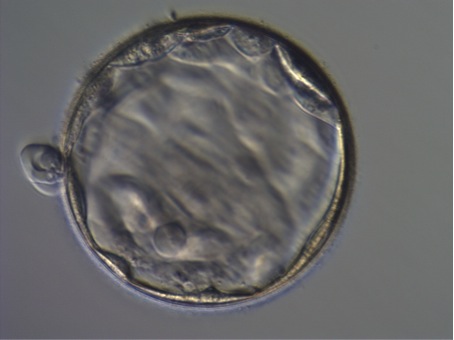

mir wurde jetzt in zwei aufeinanderfolgenden Zyklen jeweils eine BC transferiert. Die Embryologin hat beide Mal die BCs als "excellent" bewertet. Im Frischversuch war es eine schlüpfende (unteres Bild,morgens um 7 Uhr, TF war um 12:30 Uhr), im Kryoversuch dann eine expandierte (Bild oben, 10:00 Uhr, ca. 2,5 Stunden nach Auftauen, TF war um 13:00 Uhr).